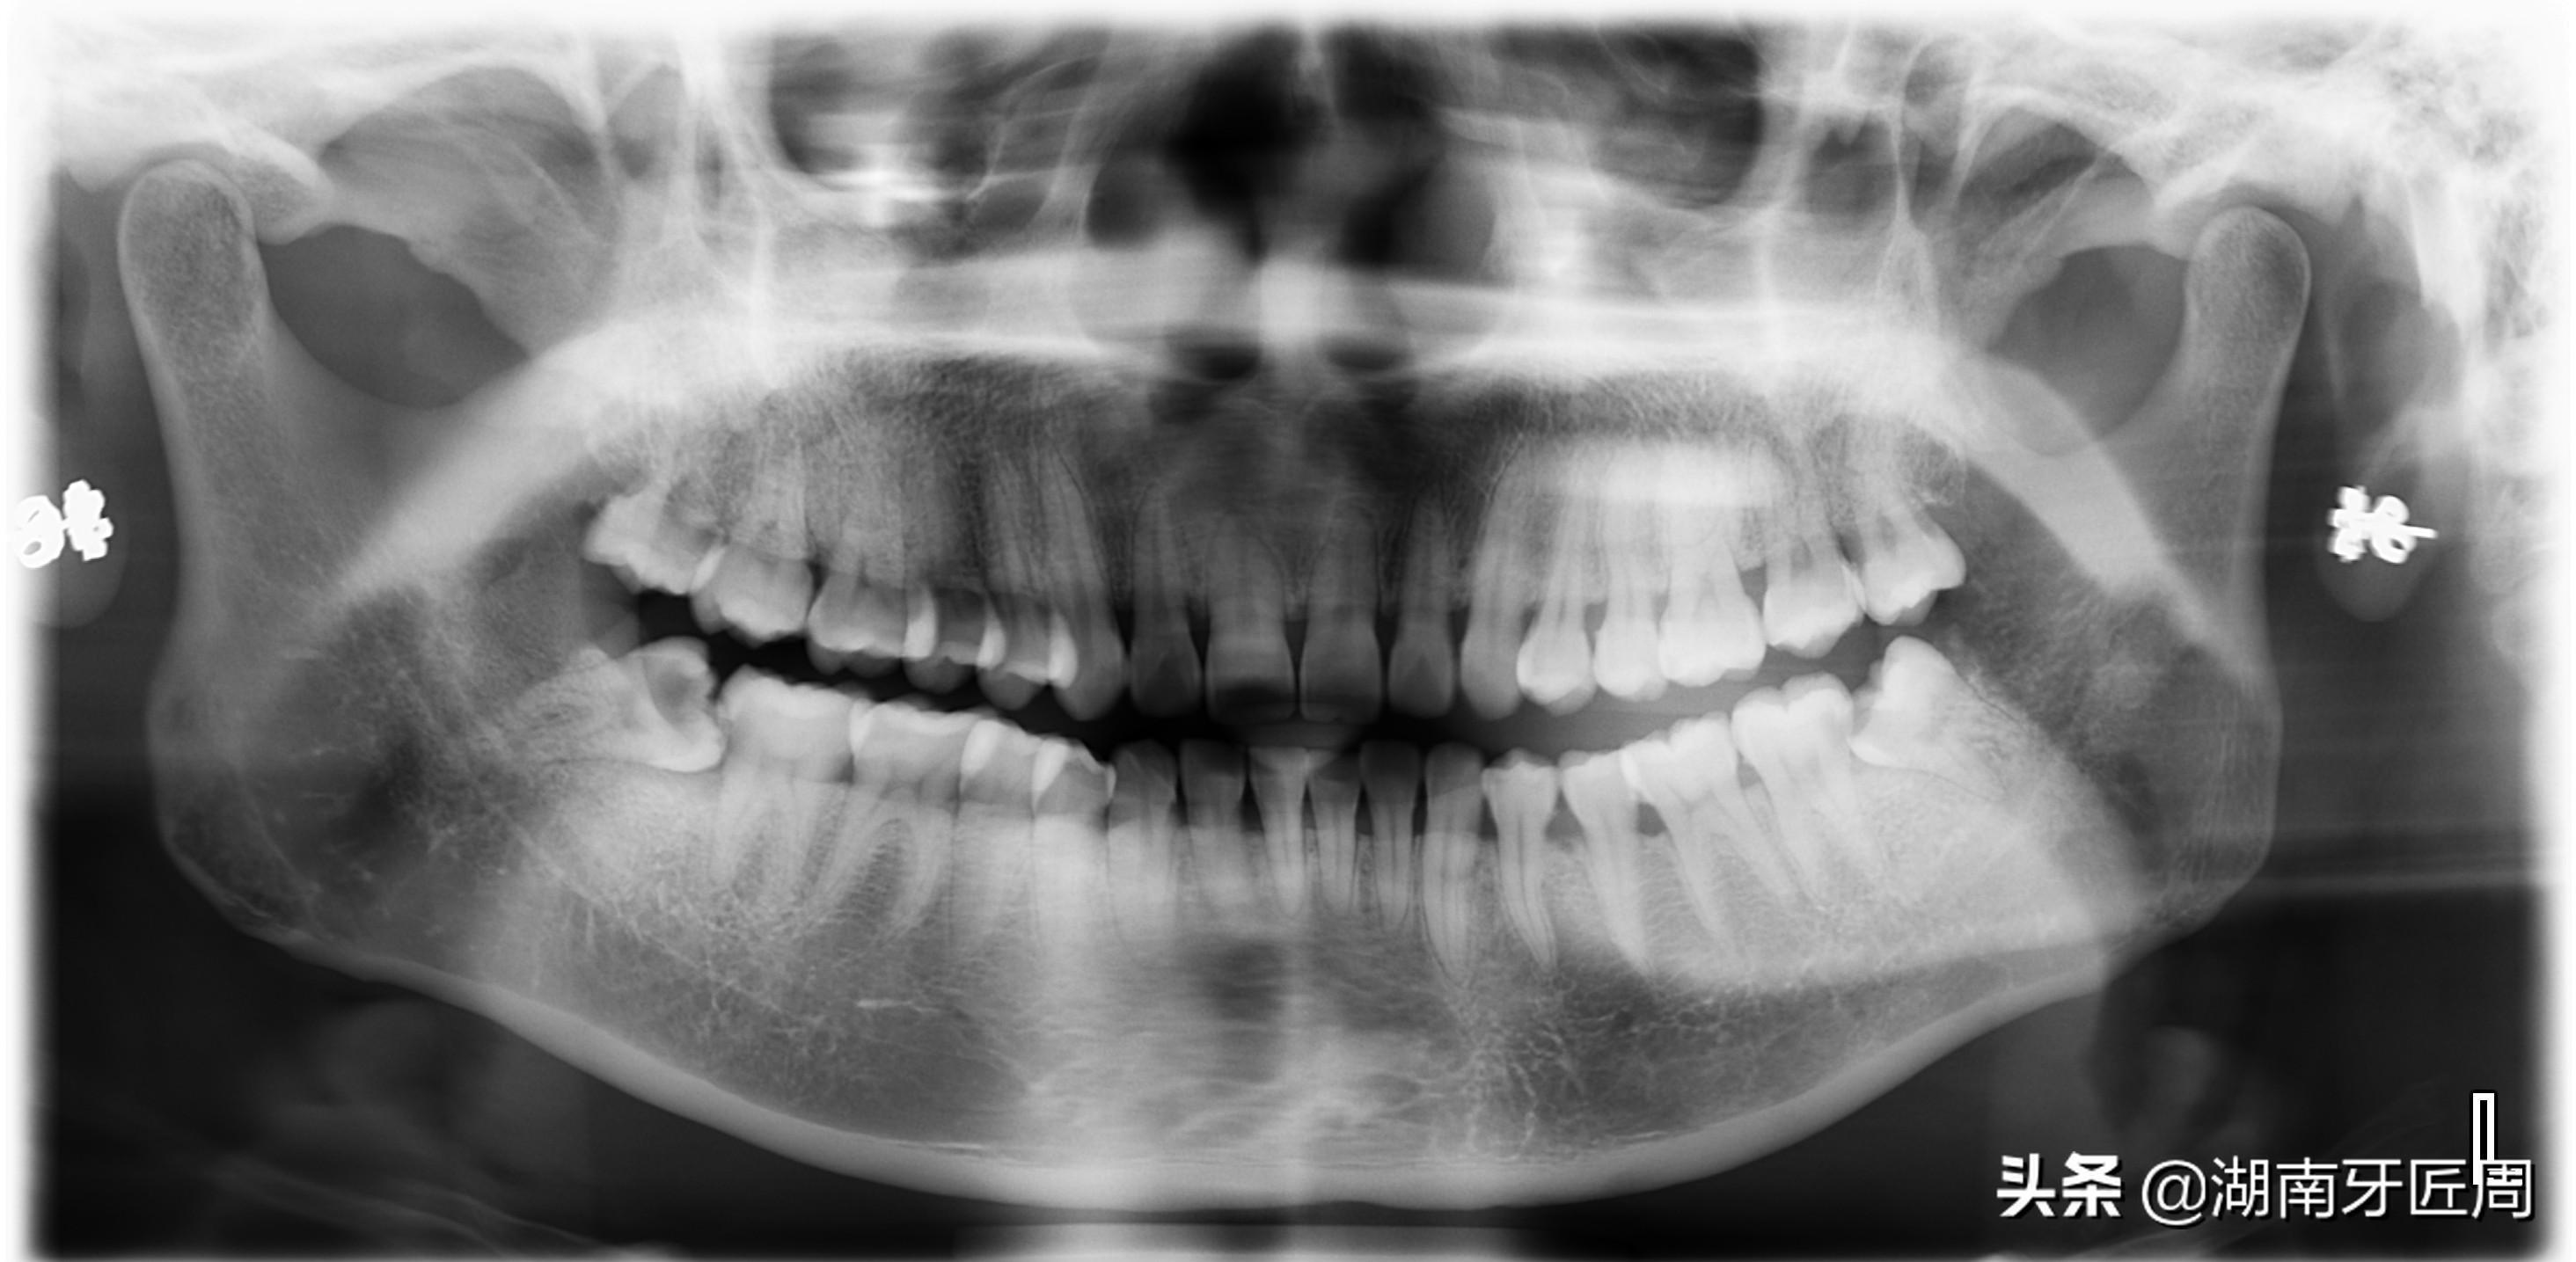

图片7两侧下颌智齿阻生

图片8

阻生的智齿可以引起牙列不齐,冠周间隙感染,张口困难,第二磨牙龋坏,严重的还可引起颌骨骨髓炎等。

如果发现有智齿阻生,并反复引起发炎的,就应该早日拔除,以免引起其它症状或疾病,如果已形成智齿冠周炎,应给予抗生素治疗,待炎症控制后再行拔除。